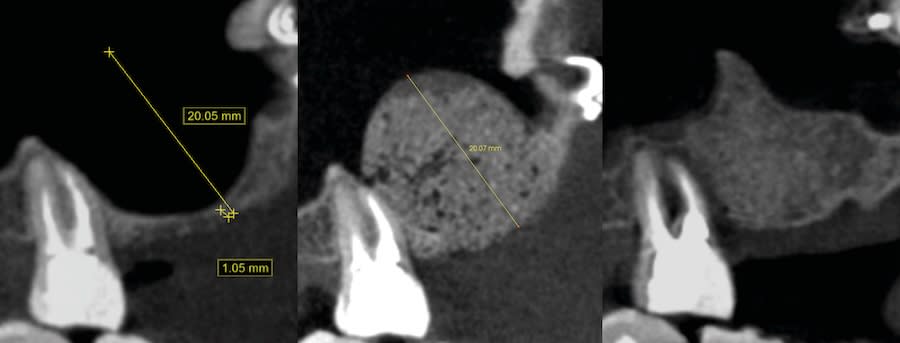

Case 1 (Figure 3 through Figure 24) depicts a 3-year follow-up of combined osseodensification sinus protocol IV in a severely resorbed maxillary ridge with ≤0.5 mm bone height in molar sites and horizontal deficiency at the first premolar site, using a two-stage approach for implant placement.